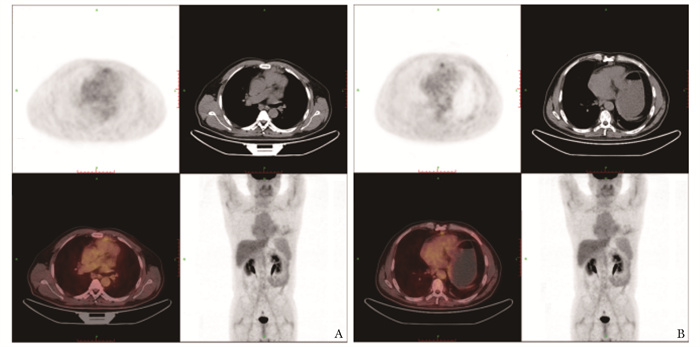

结果  患者为中年男性,是目前国内外报道的首例被诊断为胸腺原发上皮肌上皮癌的患者。该患者经手术、化疗、放疗、分子靶向治疗等综合治疗后仍出现疾病进展,从手术确诊至死亡时间为22个月。

Results  The patient was a middle-aged male diagnosed with primary EMC of the thymus, and he was the first case currently reported at home and abroad. Even though the patient received comprehensive treatments including surgery, chemotherapy, radiotherapy and molecular targeted therapy, he still experienced disease progression, with a survival time of 22 months after surgery.